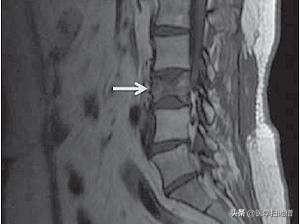

我们一天工作劳累后。第二天常会感觉到腰酸背痛。这是很正常的反应。但47岁的何先生就没那么幸运了。近段时间何先生一直感觉自己的背痛。因为之前做过肺癌切除术。所以对自己的身体格外重视。去医院做了肺部的检查。并没发现有肿瘤复发的痕迹。但是医生建议他好好检查一下胸椎。随后通过核磁共振检查。何先生被确诊为胸椎转移瘤。

对于一些疾病我们如果能在早期发现。其治愈几率是很大的。所以我们要养成定期体检的习惯。此外。还需选择正确的体检方式。对于肺部。最佳检查方式是肺部CT。前列腺是抽血检查PSA和核磁共振检查。乳腺则最好选择钼靶和彩超。如果排除胸椎转移。最佳方式是胸椎MRI或骨扫描。